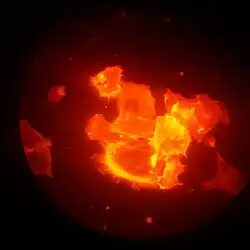

Des cellules MYF (cellules cancéreuses) ont été cultivées dans un milieu riche en blebbistatine (drogue inhhibant la contraction du complexe acto-myosine). Leur forme peut être déterminée au microscope grâce aux filaments d'actine marqués en rouge. Mai 2018.